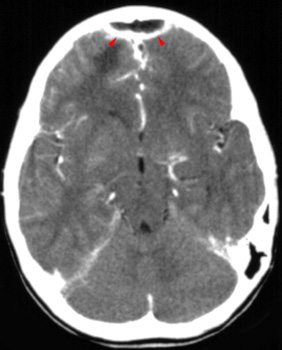

On CT, an epidural abscess appears as a focal low-density epidural mass. Dural enhancement may be present as well. The mass may extend into the subgaleal space. It also may cross the midline but usually does not cross suture lines.

![]() ![]() In the left image

notice the rim enhancing epdural fluid collection (arrowheads). In the